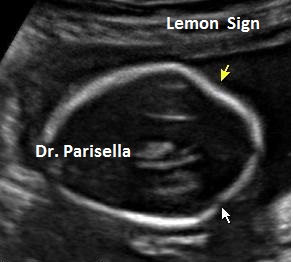

3) segno del limone;

I primi tre segni (segno del limone, obliterazione della cisterna magna, cervelletto a banana), c.d. segni indiretti, hanno una elevata sensibilità nella diagnosi dei difetti aperti e sono espressione della sindrome di Chiari tipo 2. Questa è la conseguenza della perdita di liquido cefalo-rachidiano attraverso il difetto spinale; la diminuzione della pressione idrostatica provoca iposviluppo della fossa cranica posteriore con conseguente erniazione del tronco encefalico e del cervelletto che si piega assumendo il classico aspetto a banana. La perdita di liquido cerebrospinale attraverso il difetto spinale provoca un aumento dei livelli di alfa-fetoproteina nel liquido amniotico e nel siero materno.